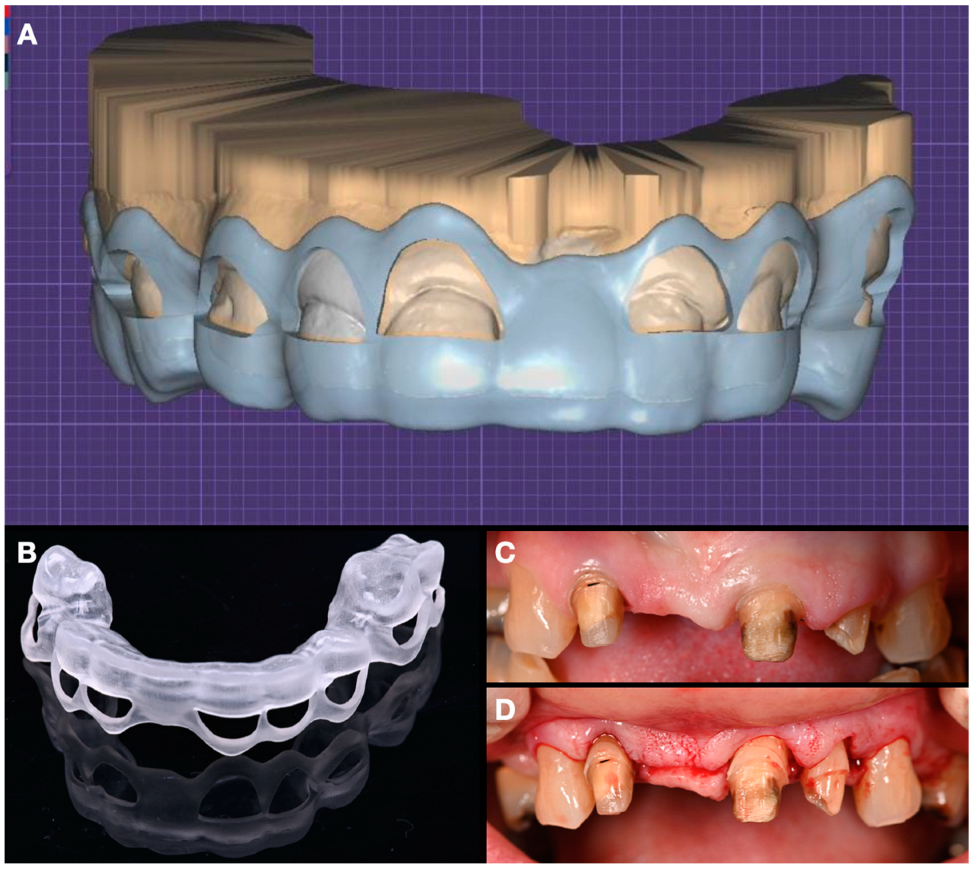

The intraoral diagnostic mock-up was performed based on the digital wax-up (Figure 5). The patient approved the appearance of the proposed restorations in the mock-up and accepted proceeding with the crown-lengthening procedure. The crown-lengthening procedure was digitally planned and guided by a printed surgical stent (Figure 6).

Figure 6. Crown lengthening phase. (A) Design of the guide. (B) Printed surgical guide. (C) Before surgery. (D) After surgery.

The provisional restorations were milled out (i.e., subtractive manufacturing) of polymethyl methacrylate (PMMA). After four months of healing time, tooth preparations were refined, final digital impressions (iTero Element 5D, Align Technology, Inc, San Jose, CA, USA) were taken, and the final restorations were designed (DentalCAD 3.1, Exocad GmbH, Darmstadt, Germany) (Figure 7).